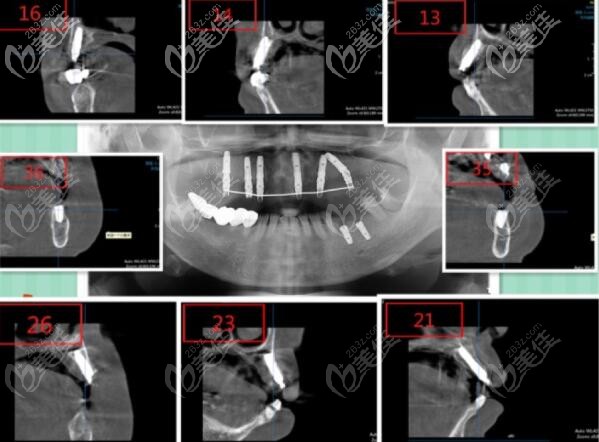

今天就來(lái)分享一份三亞鼎點(diǎn)口腔做的韓國(guó)登騰Dentium上頜all-on-6即刻負(fù)重種植牙案例,看看這位63歲的高齡老人,做完活動(dòng)假牙后為什么又選擇了種植牙呢?

三亞鼎點(diǎn)口腔做的all-on-6半口即刻負(fù)重種植牙真實(shí)案例:

癥狀:口腔檢查上半口只剩下兩個(gè)殘冠。

醫(yī)生設(shè)計(jì)的方案是:上頜韓國(guó)登騰做ALL-ON-6即刻負(fù)重,6個(gè)月后進(jìn)行全瓷冠固定修復(fù)。

用的韓國(guó)登騰種植體,因?yàn)榈球v種植牙對(duì)于牙槽骨吸收病例在臨床上也有很高的成功率,而且性?xún)r(jià)比高,顧客也可接受。